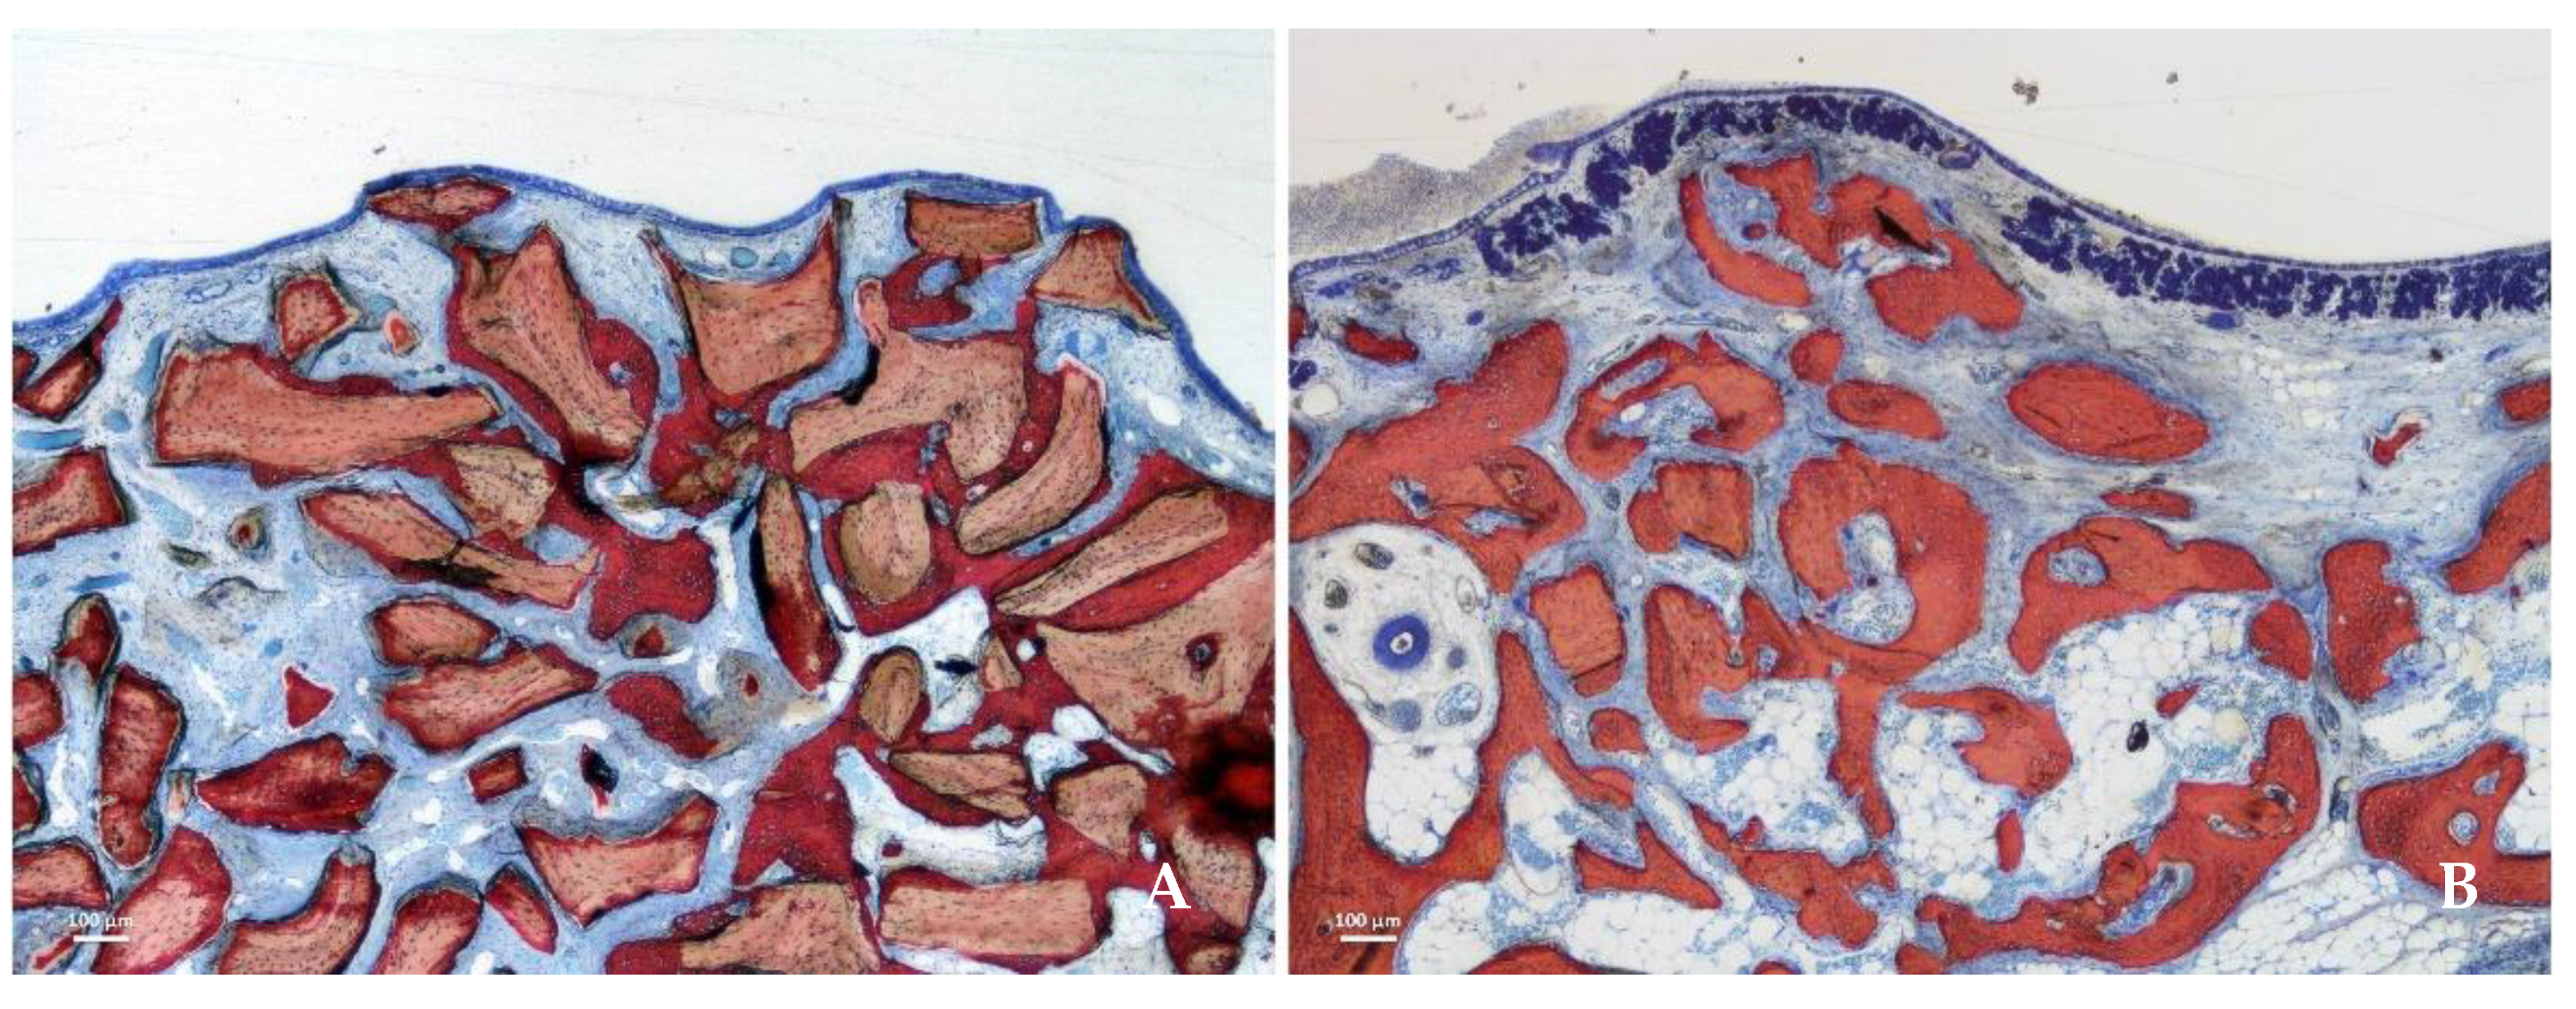

3. Results